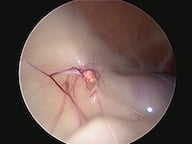

Endoscopia Rígida

A Clínica Veterinária de Albufeira já disponibiliza serviços de minima invasão como solução alternativa às cirurgias tradicionais, sejam estas profiláticas (como as ovariohisterectomias, orquiectomia de criptorquideos) ou de diagnóstico (biópsia, cistotomias, etc). A mais valia desta técnica é a utilização de orifícios naturais ou incisões minímas para aceder ao sistema desejado ( urinário, respiratório, digestivo, reprodutivo), sendo a recuperação mais rápida e a dor pós operatória muito menor.